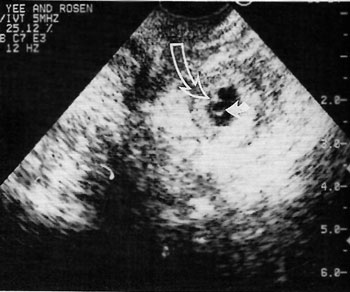

Εικόνα 4. Ζωντανό έμβρυο

και λεκιθυκός σάκος στο εξάρτημα.

Ζωντανό εξωμήτριο έμβρυο

Η εμφάνιση ενός ζωντανού εμβρύου στα εξαρτήματα είναι το πιο συγκεκριμένο υπερηχογραφικό

σημείο (εικόνα 4). Η ευαισθησία αυτού του σημείου, ωστόσο, έχει αυξηθεί με την

πάροδο των χρόνων, πιθανώς εξαιτίας της ανώτερης ανάλυσης με το διακολπικό υπερηχογράφημα.

Ο Mahony επισήμανε ζώντα έμβρυα στα εξαρτήματα στο 11% των έκτοπων κυήσεων,

σε μια διακοιλιακή υπερηχογραφική μελέτη.(27) Πιο πρόσφατες μελέτες, με σημαντικά

χαμηλότερους δείκτες σαλπιγγικής ρήξης και με χρήση διακολπικού υπερηχογραφήματος,

αναφέρουν μεγαλύτερο ποσοστό υπερηχογραφικά ορατών ζώντων εξωμήτριων εμβρύων,

από 15% έως 23%.(26-28)